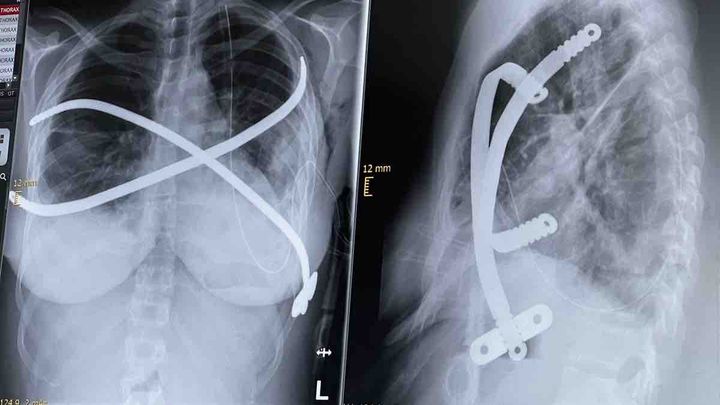

Living in Germany, I spent a transformative year studying at Georgia Southern University in the south of the USA, immersing myself in new cultures and perspectives. But tragedy struck with medical malpractice that spiraled into complications from my severe pectus excavatum — a congenital chest wall deformity where the breastbone (sternum) and ribs grow abnormally inward, creating a deep, sunken “funnel chest” that compresses the heart and lungs.

My Haller index — a key measure of severity calculated from chest imaging as the ratio of chest width to the narrowest front-to-back depth — worsened dramatically from 7.5 to 9.5. A normal range is around 2.5, mild cases are 2-3.25, moderate 3.25-3.5, and anything over 3.5 (especially >7) is considered severe, requiring surgery.

After five failed surgeries, my body is barely holding on as I await recovery for a sixth reconstructive procedure.